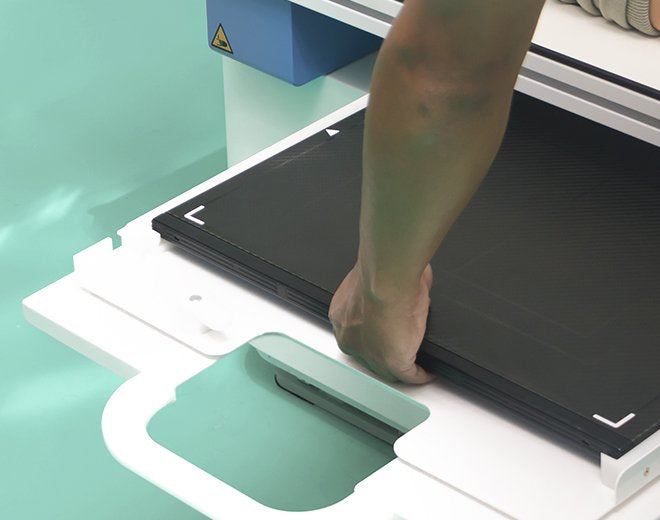

Gigantic Bag’s X-Ray Cassette Covers are designed to protect x-ray cassettes from damage and contamination, ensuring safety and cleanliness in medical environments. These single-use, disposable covers are made from durable, fluid-impervious polyethylene plastic, providing an effective barrier to stop the spread of infection and protect equipment from fluids. Ideal for use in emergency rooms, operating rooms, or with portable x-ray units, these covers deliver trusted performance when it matters most.

Ideal for Medical Applications:

Emergency Rooms:

Protect x-ray cassettes in high-pressure, fast-paced environments where hygiene and safety are critical. -

Operating Rooms:

Maintain sterility and prevent fluid damage during surgical procedures with disposable covers. -

Portable X-Ray Units:

Ensure cleanliness and safety when using mobile imaging equipment in varied locations. -